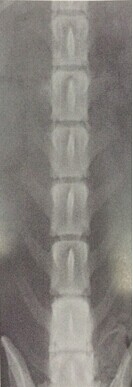

图4.2.3 B椎间盘侧方一切正常X线片